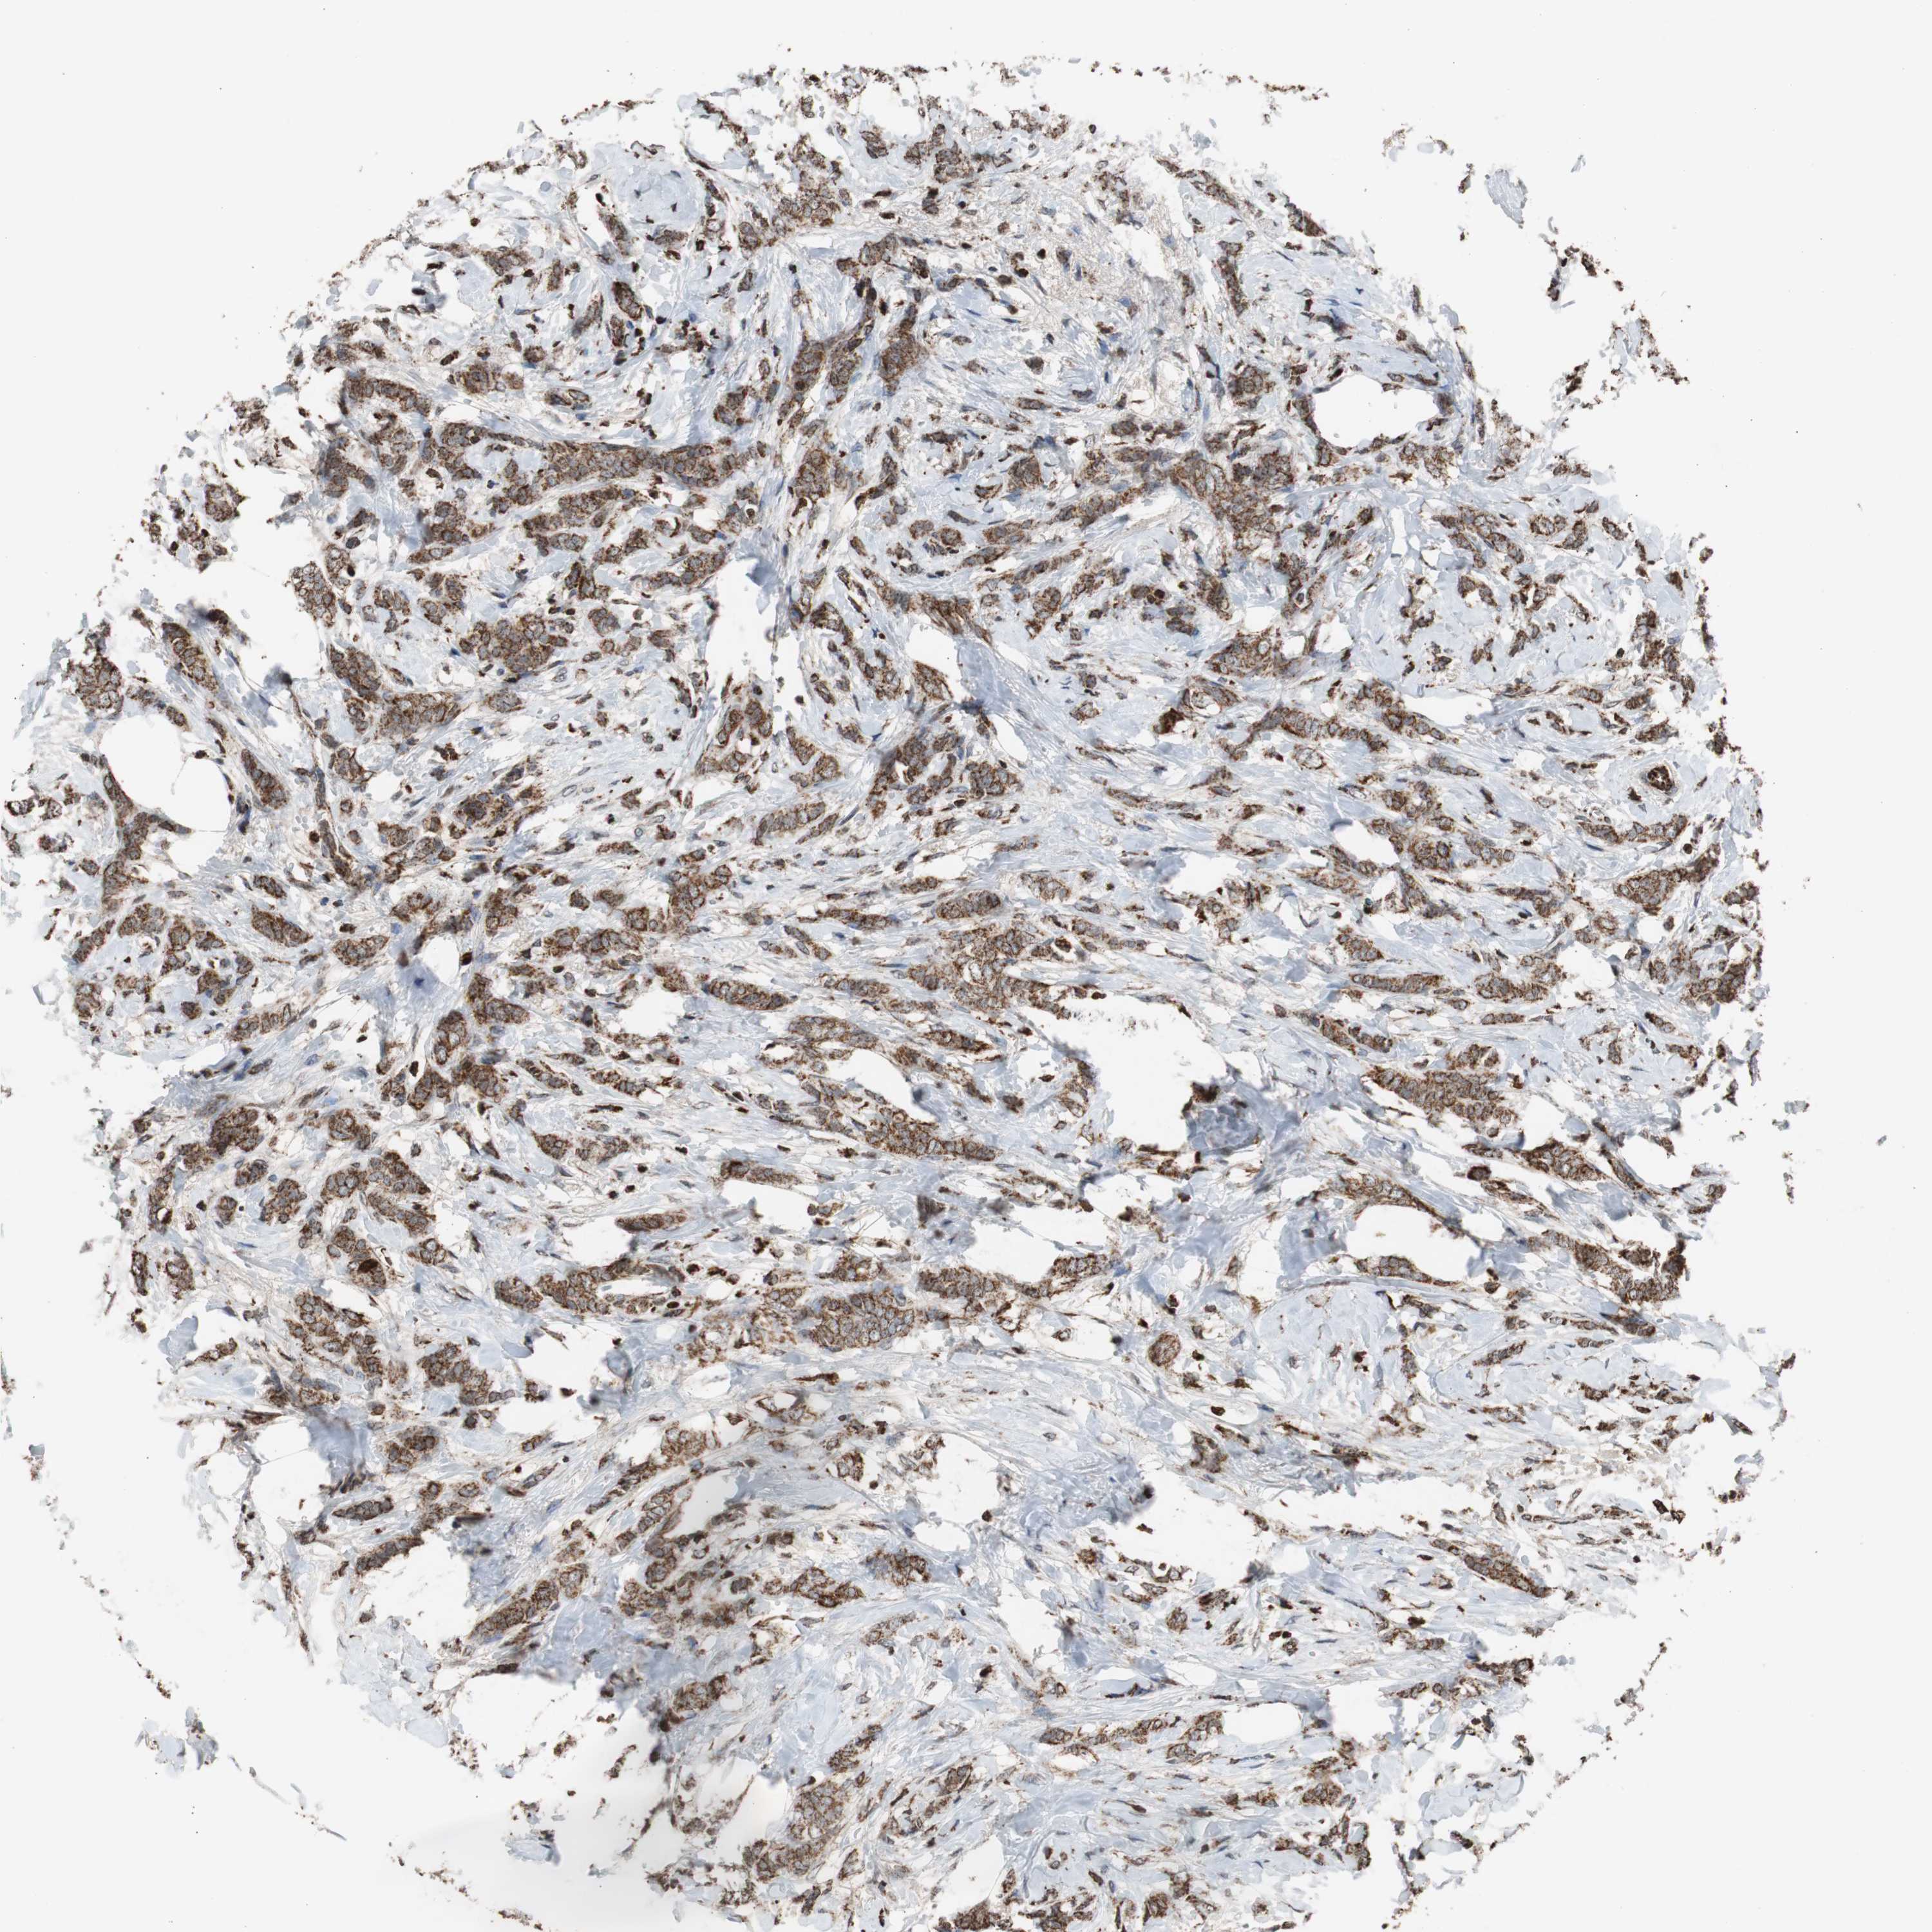

CANCER BREAST CANCER Show tissue menu

BRCA TCGA BRCA VALIDATION PROTEIN EXPRESSION